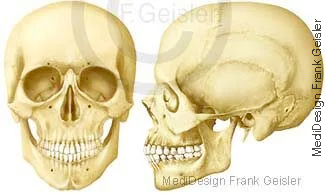

Schädelknochen von vorn und seitlich; Rumpfskelett mit oberen Extremitäten frontal und dorsal

Die Grundlage des Kopfes (Caput) bildet der Schädel (Cranium), zu dem auch das Zungenbein (Os hyoideum) und die Gehörknöchelchen (Ossicula auditus) gerechnet werden. Der Gehirnschädel (Neurocranium) umschließt die Schädelhöhle (Cavitas cranii), in der sich das Gehirn (Cerebrum) befindet. Der Gesichtsschädel (Viszerocranium) besteht eigentlich aus dem Nasenskelett und Kieferskelett. Er besitzt als einzige äußere bewegliche Verbindung das Kiefergelenk (Articulatio temporomandibularis).

Das Rumpfskelett wird von Wirbel (Vertebrae), Rippen (Costae) und dem Brustbein (Sternum) gebildet. Das Skelett besitzt Stützfunktionen für den Rumpf und die Extremitäten, liefert Ursprungsstellen und Ansatzstellen für die Skelettmuskulatur und Gelenkkörper für seine Beweglichkeit. Die Schädelknochen umgeben schützend das Gehirn, die Wirbel das Rückenmark, der Brustkorb bildet einen Schutz für die Brustorgane und das Becken für die Beckeneingeweide. In den Markhöhlen im Innern der Knochen befindet sich das Knochenmark. Die Anzahl der das Skelett bildenden Knochen verändert sich während des Lebens. Einige, die ursprünglich getrennt angelegt werden, vereinigen sich im Verlauf der Skelettentwicklung miteinander.

Im mittleren Lebensalter besteht das Skelett eines Menschen aus mehr als 200 einzelnen Knochen. Die Wirbelsäule (Columna vertebralis) setzt sich aus 24 Wirbeln (Vertebrae), dem Kreuzbein (Os sacrum) und dem Steißbein (Os coccygis) zusammen. Das Kreuzbein bildet sich durch die Verschmelzung von fünf einzelnen Wirbeln, das Steißbein entsteht aus zwei bis sieben Wirbelrudimenten. Zum Stammskelett gehören außerdem das Brustbein (Sternum) und die zwölf Rippenpaare (Costae). Das Kopfskelett, der Schädel (Cranium), besteht insgesamt aus 33 einzelnen Knochen, davon werden 15 dem Hirnschädel und 18 dem Gesichtsschädel zugeordnet. Zum Schultergürtel gehören jeweils rechts und links das Schlüsselbein (Clavicula) und das Schulterblatt (Scapula). Die obere Extremität wird gebildet vom Oberarmbein (Humerus), der Speiche (Radius), der Elle (Ulna), acht Handwurzelknochen (Ossa carpi), fünf Mittelhandknochen (Ossa metacarpalia I-V) und vierzehn Fingerknochen (Ossa digitorum manus).